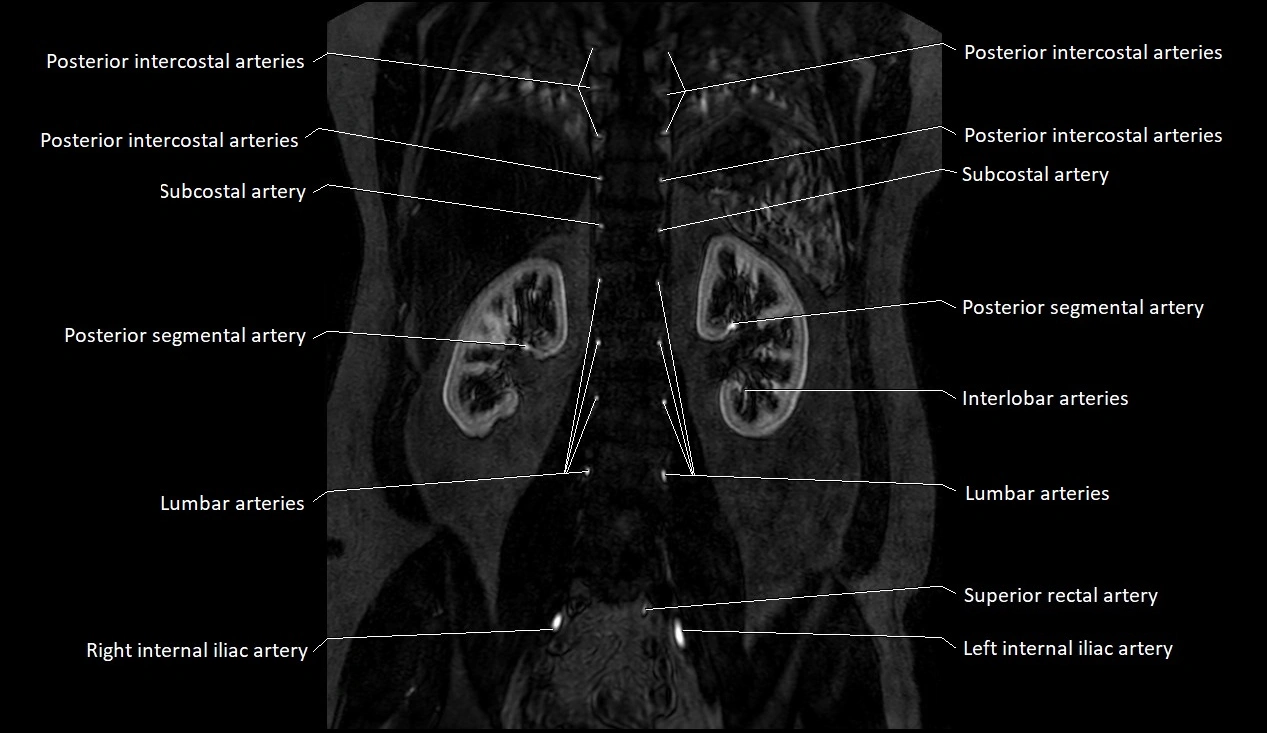

CT images

image